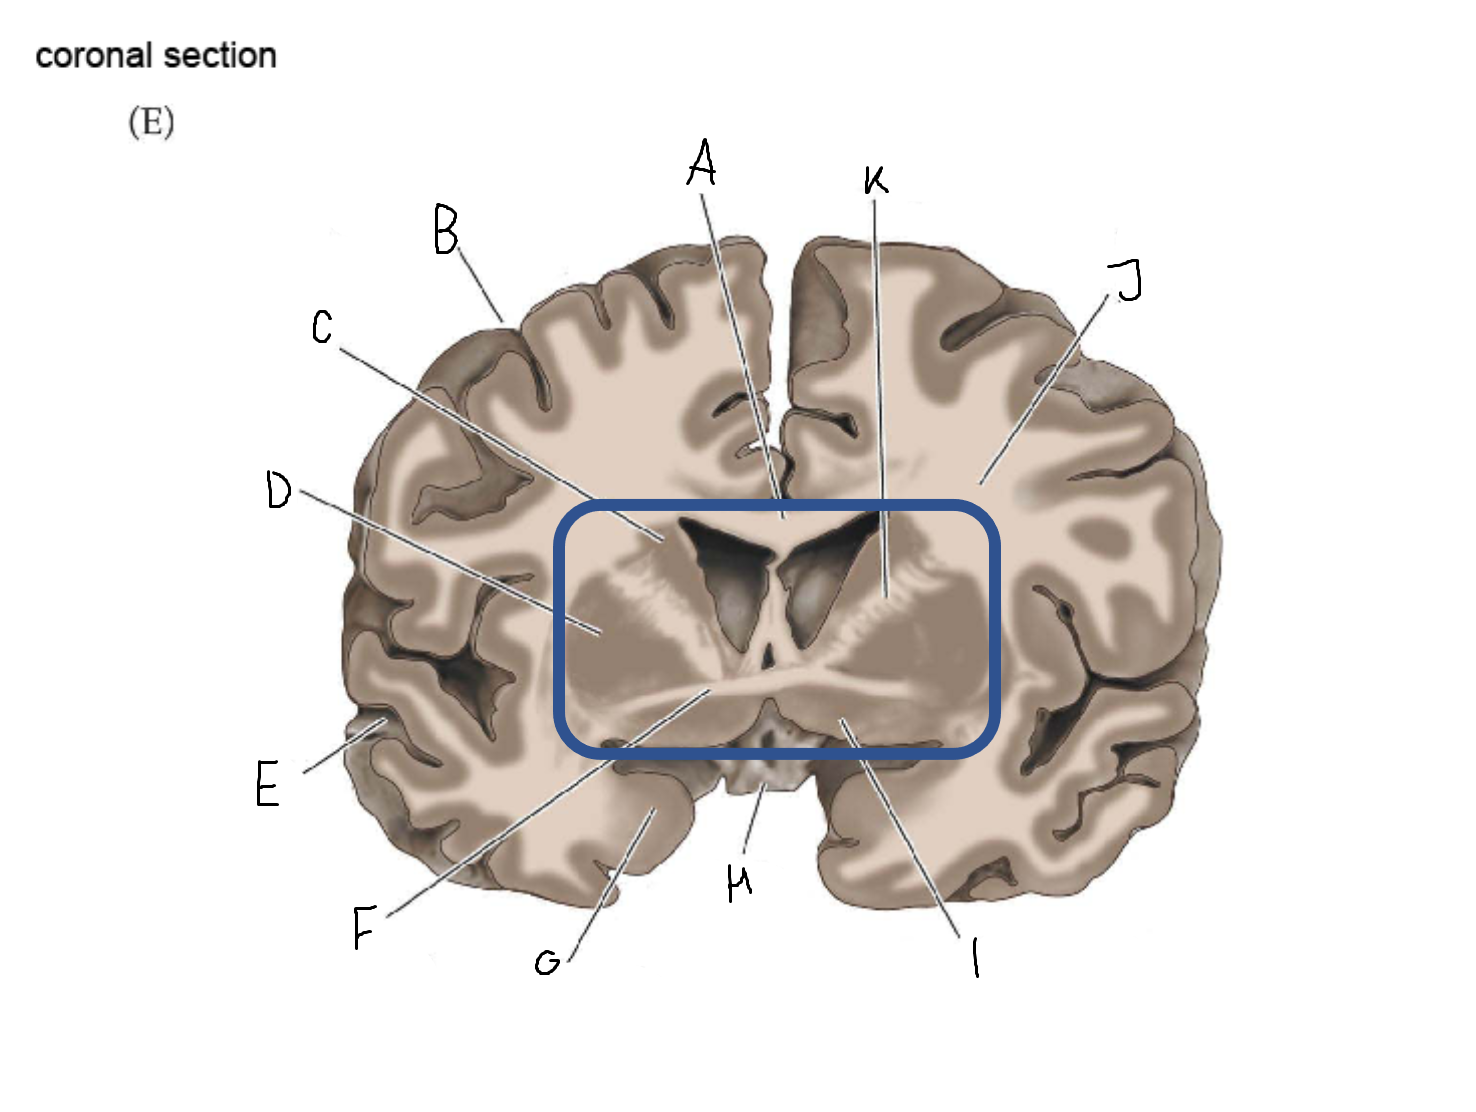

B

anterior horn of lateral ventricle

C

head of caudate nucleus

D

internal capsule (anterior limb)

E

putamen

F

globus pallidus

G

Thalamus

H

External capsule

I

internal capsule (posterior limb)

J

tail of caudate nucleus